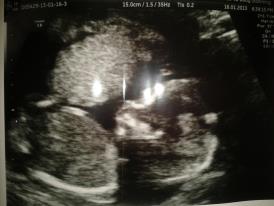

this is our 16 week scan pic....really need opinions :) thanks xx

Can't tell gender from this photo :(. Did you get a potty shot?

no we dnt get the option, she was so quick with the scan...:( any skull theory? x

No nub :(

No nub in this pic, maybe boy skull